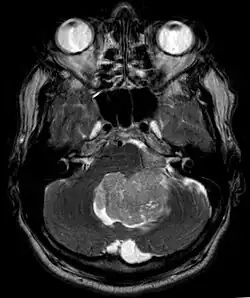

Ependymoma of 4.ventricle in MRI. -